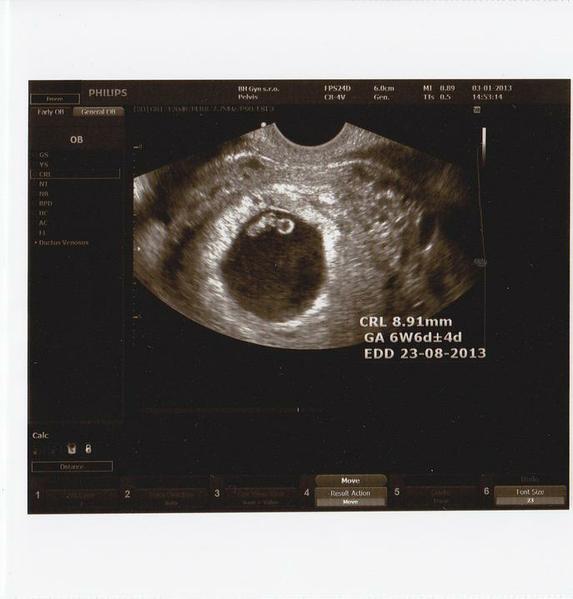

fíha, vy ste sa tu ale rozšupli, ani to nebudem všetko čítať... 😅 ja som bola včera u lekárky, tak malinké je v poriadku, je to 7tt, srdiečko krásne bilo, tak máme obrovskú radosť. dnes je mi už aj trošku lepšie, tak to už hádam takto zostane a nebude sa to zhoršovať.....